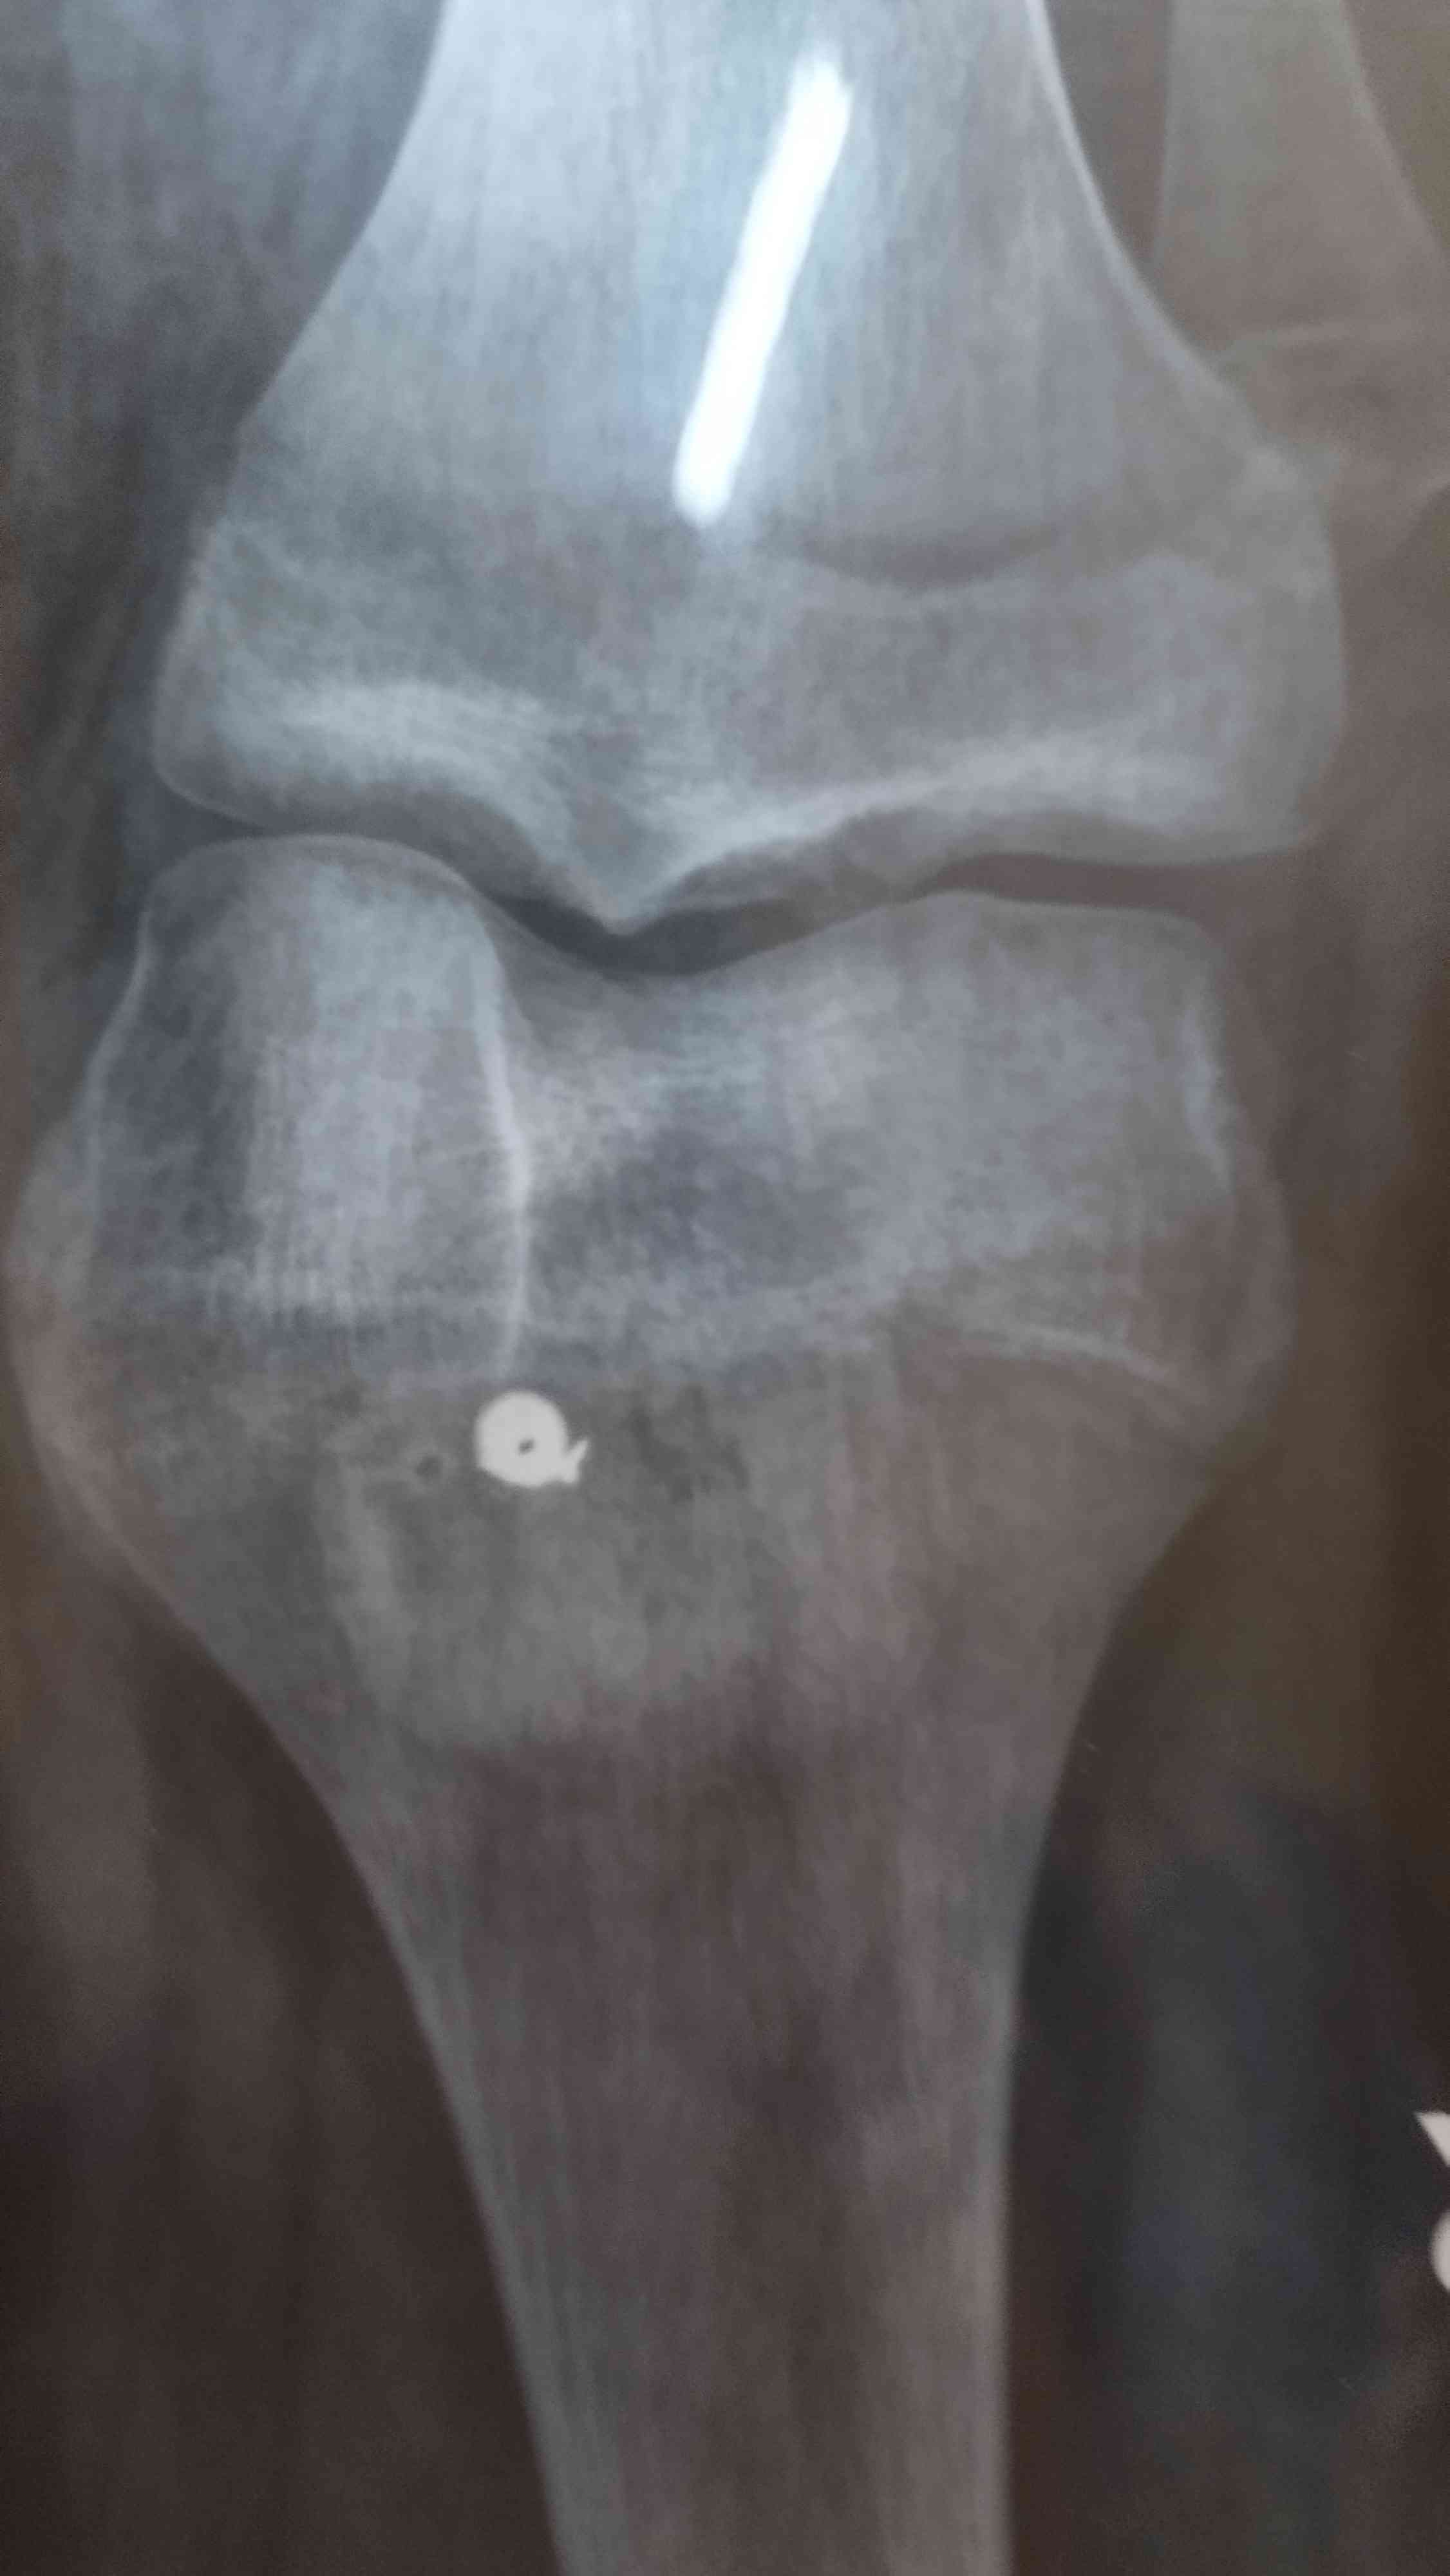

اجريت عملية تثبيت كسر صابونه و تثبيت صابونه والان انا في يوم 18 بعد عملية هل ابد تمارين ثني ركبة مع العلم لدي تمزق جزيي برباط صليبي وضعت صور الاشعه...